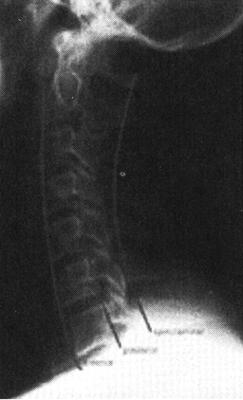

图7-1 正常颈椎X线侧位片:正常颈椎前、中、后三柱连线光滑连续,中、后柱连线之间为脊髓所在

图7-2 C5以上前脱位,中、后柱连线显示在C5水平处明显狭窄,表明颈髓在此处受压